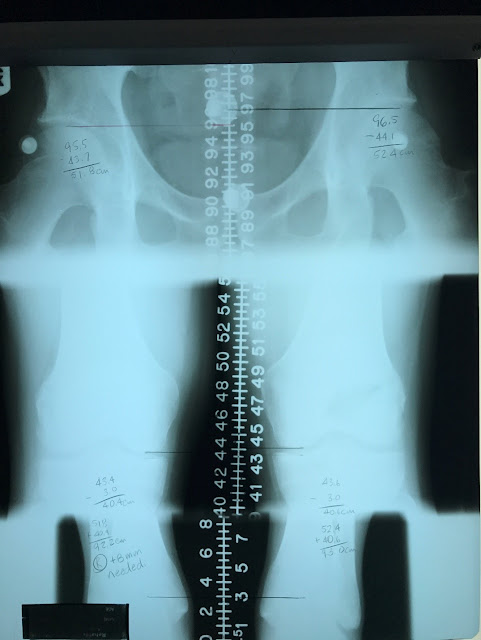

process by visiting a chiropractor. Symmetry is important when considering

injury prevention or injury recovery. It’s important to examine and address leg

length inequalities. In the bone length study below, by looking only at the

patient’s hips it appears they are about 1cm off. BUT by performing this xray

which is the gold standard for measuring leg length, it includes the length of

the right and left femur and tibia, now you have very specific information that

will allow you to determine the exact needs of a runner. For example, this

patient requires an 8mm lift on the right side. If we only paid attention to

the hips or tried using a tape measure externally, we would be doing them an

injustice and possibly putting them in harms way!